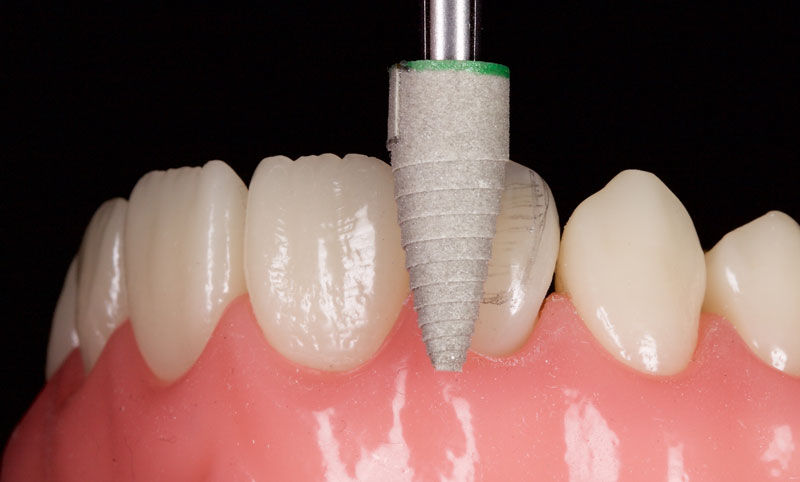

- Minimal tooth preparation/reduction (Fig. 6): This is employed when orthodontics is declined or if the patient already has a Class I incisal relationship with an acceptable overjet and overbite.

This is best achieved by cutting uniform 1.0 mm-deep cuts (dimples or grooves). The tooth is then reduced with a coarse crown diamond, followed by polishing with fine diamonds/discs to smooth the enamel and reduce the risks of white lines due to “enamel peel” (cohesive enamel failure). Typically, only the incisal-facial half must be reduced, leaving the gingiva untouched.